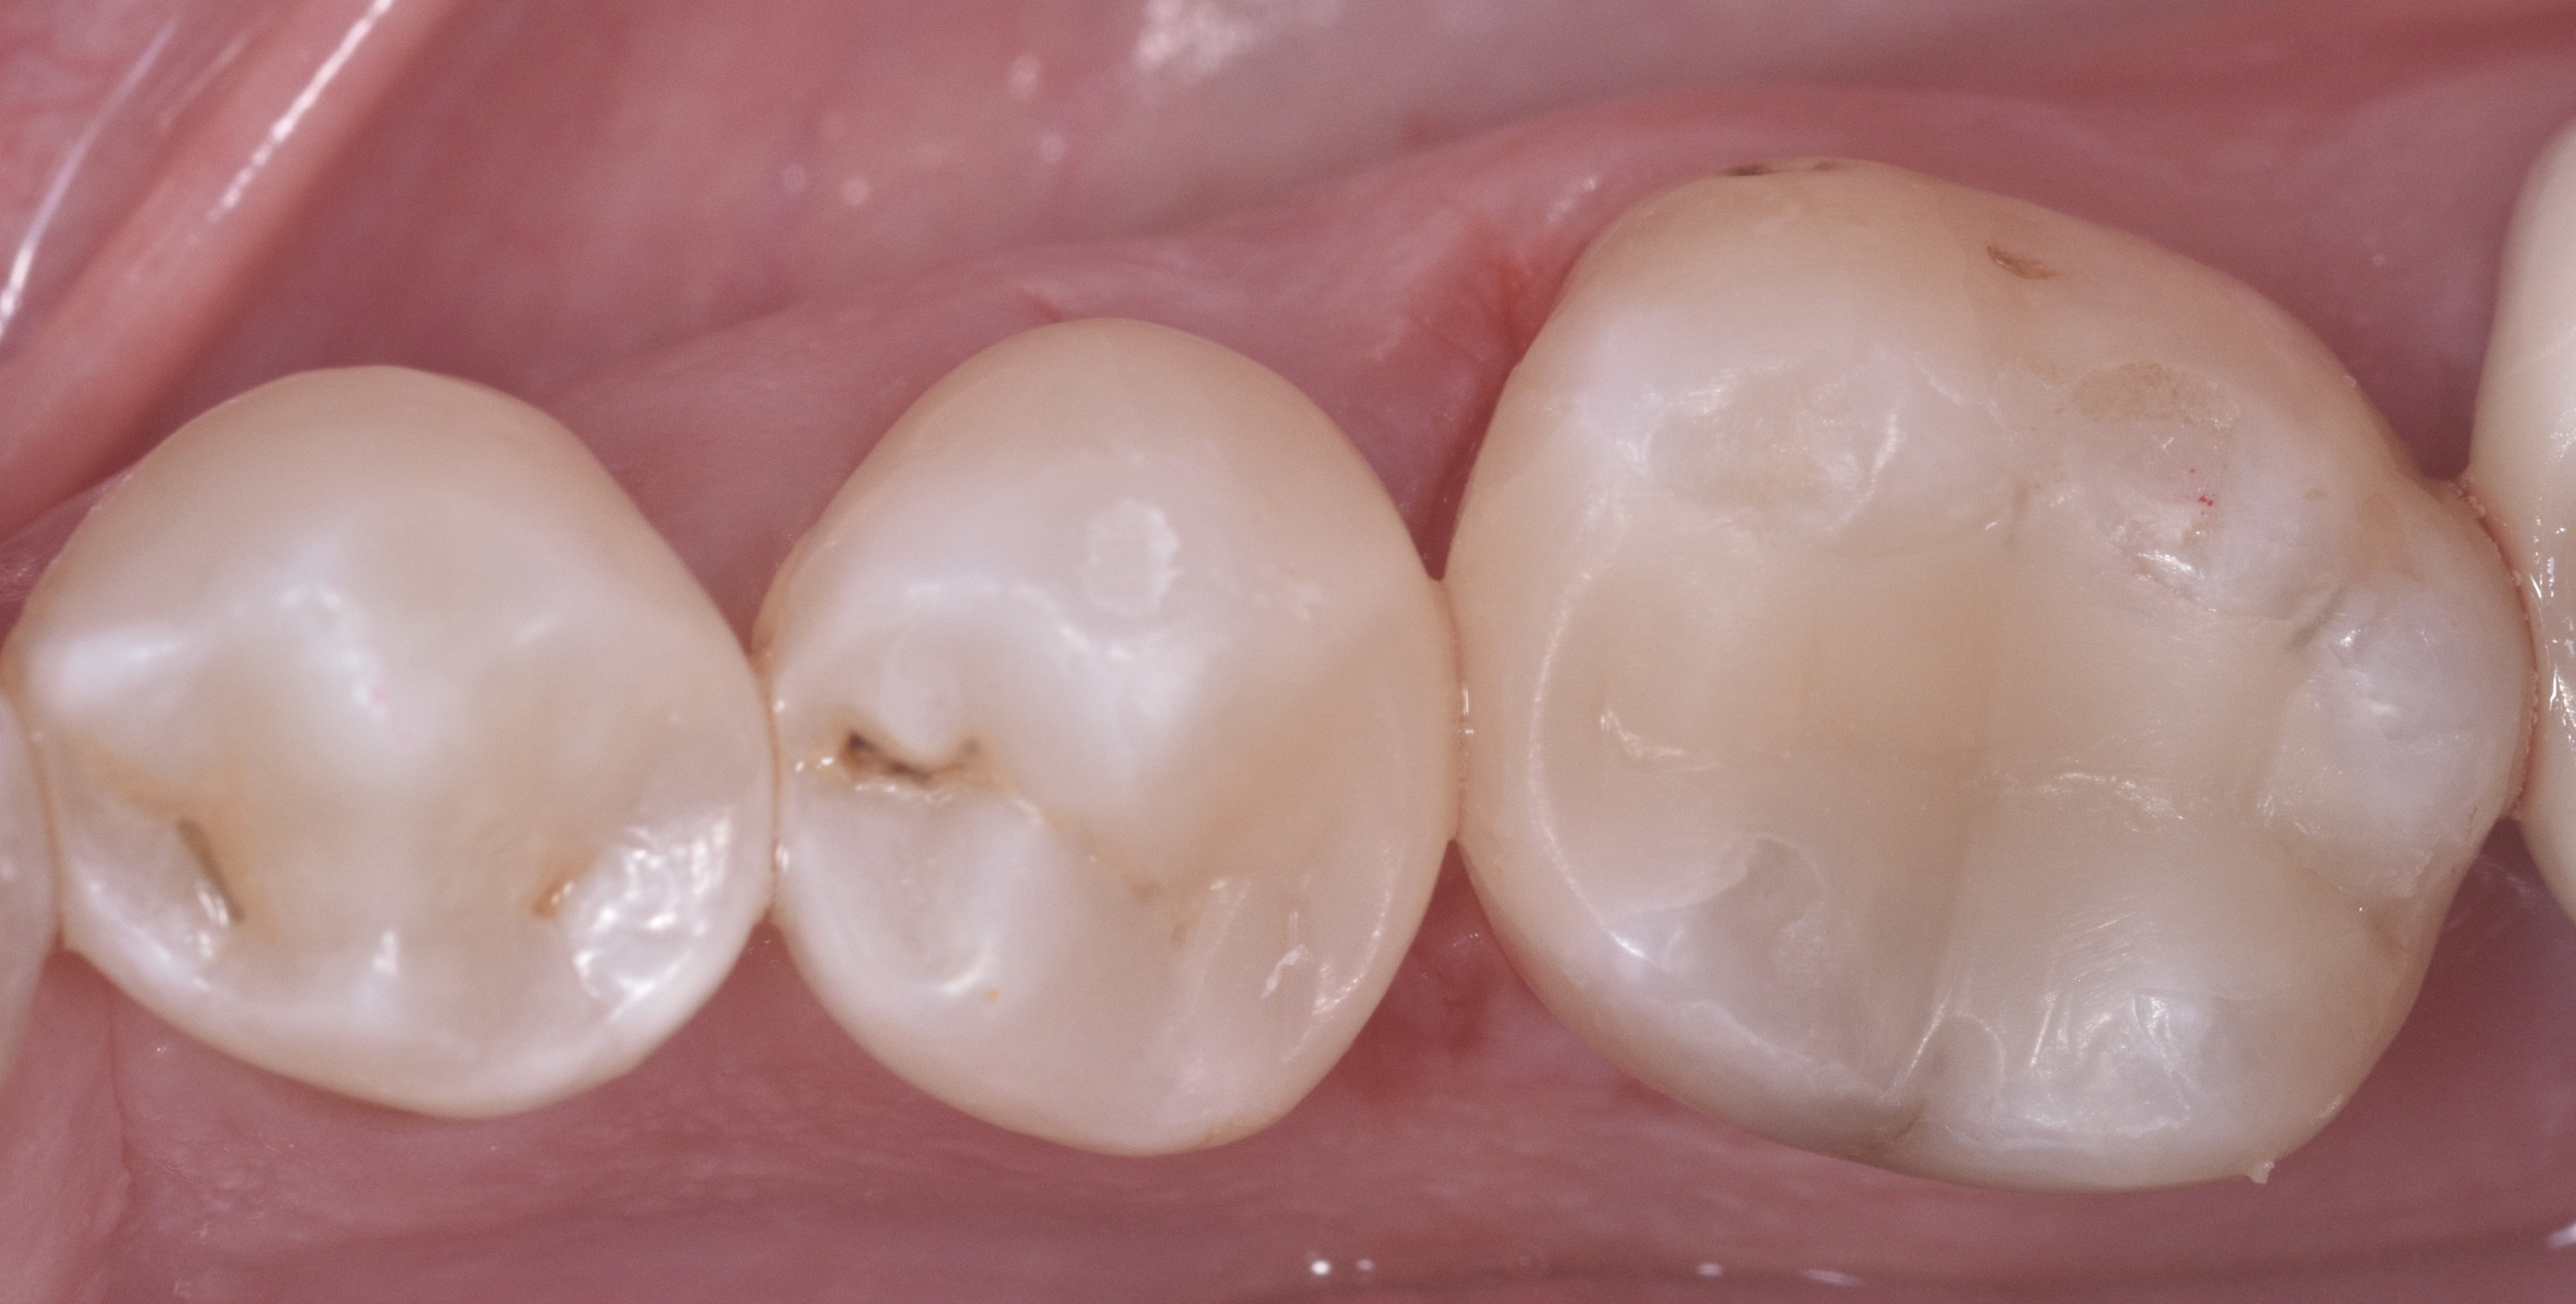

A 51-year-old man in good health came to my office with large carious lesions between teeth #29 (DO) and #30 (MO). As seen in the pre-op photo (Figure 1), this case was challenging because both teeth were rotated: tooth #29 was rotated toward the lingual and #30 toward the buccal, creating wide embrasures and a relatively small contact area.

Figure 1

Figure 1. Patient presented with large carious lesions between teeth #29 (DO) and #30 (MO).